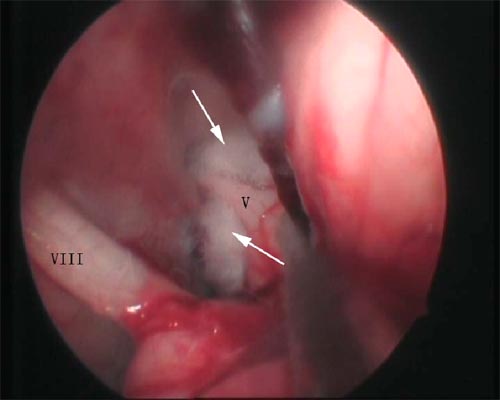

神经内镜辅助下三叉神经微血管减压术

术前三叉神经(V)被责任血管压迫(↑所示)